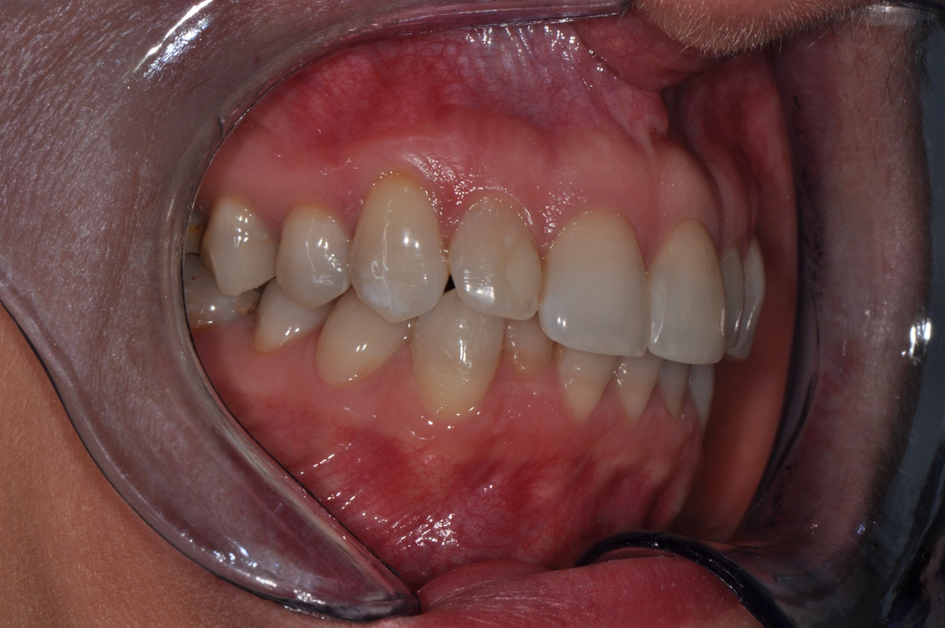

Wykonano zdjęcia uzębienia pacjentki (ryc. 2‑4). Przeprowadzono dokładne badanie mięśni żucia, zbadano ruchy żuchwy w trzech płaszczyznach – ruch otwierania jamy ustnej, ruch doprzedni oraz ruchy doboczne. Podczas otwierania zaobserwowano zbaczanie żuchwy w połowie ruchu, a następnie powrót do linii prostej. Bolesność mięśni żucia, stłoczenie zębów oraz nieprawidłowy tor ruchu żuchwy podczas otwierania nasuwał podejrzenie występowania problemów okluzyjnych.

Ryc. 4. Zdjęcie w pozycji maksymalnego zaguzkowania – strona prawa.